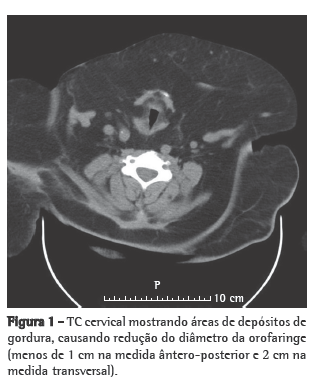

As condições clínicas do paciente melhoraram progressivamente, com a subsequente redução das pressões BiPAP e do uso do ventilador, que foi interrompido no 6º dia de internação em virtude do aparecimento de ulcerações faciais causadas pela máscara nasal. Durante a primeira noite sem ventilação não-invasiva, houve longos períodos de dessaturação de oxigênio (SpO2 < 88%) e ronco. O paciente foi então submetido à TC cervicofacial (Figuras 1 e 2) e a um estudo cardiorrespiratório do sono.

O estudo do sono levou aproximadamente 8 h, revelando grave apneia obstrutiva do sono (índice de apneia-hipopneia: 37 eventos/h; índice de apneias obstrutivas: 29 eventos/h; mediana de saturação periférica de oxigênio durante o sono: 88%; índice de dessaturação de oxigênio: 51%/h; e SpO2 mínima: 51%). A TC revelou várias áreas de depósitos de gordura no mediastino, causando uma redução no calibre da traqueia de 1 cm transversalmente e 4 cm ântero-posteriormente. A titulação da continuous positive airway pressure (CPAP, pressão positiva contínua nas vias aéreas) foi realizada na segunda noite, e o paciente recebeu alta. Em casa, o paciente permaneceu em ventilação BiPAP (EPAP: 8 cmH2O; IPAP: 16 cmH2O), realizada através de almofadas nasais (Figura 3).